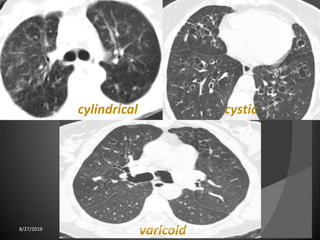

Bronchiectasis: localized bronchial dilatation.

The diagnosis is based on a combination of the

following findings:

-bronchial dilatation (signet-ring sign)

-bronchial wall thickening

-lack of normal tapering with visibility of airways in

the peripheral lung

-mucus retention in the bronchial lumen

-associated atelectasis and sometimes air trapping

8/27/2019 zannatulrayhan@gmail.com

Bronchiectasis few having air-fluid levels8/27/2019 zannatulrayhan@gmail.com

cysticcylindrical

varicoid8/27/2019 zannatulrayhan@gmail.com